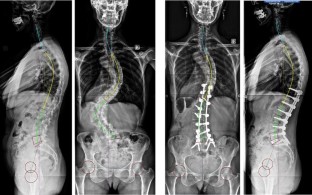

Clinical and radiological data were extracted from a prospective database of 132 AIS patients and 52 AS before and at last follow-up after surgical correction. Sagittal parameters were evaluated on AP and lateral radiographs using a custom software: pelvic incidence (PI), sacral slope (SS), pelvic tilt (PT), lumbar lordosis (LL), thoracic kyphosis (TK), C7 Barrey’s ratio, spino-sacral angle (SSA). A new algorithm of combination of balance parameters was proposed to characterize and compare the various pathological spino-pelvic settings. Based on PI subdivision in high (<55°) and low values (>55°), then on a range of PT indexed on PI giving the pelvis positioning (anteverted, normal or retroverted), the population was finally characterized by the C7 plumbline position with regard to the posterior edge of the sacrum and the center of the femoral heads, in balanced, slightly unbalanced and unbalanced. More specifically, the AIS study included the cervical shape alignment with cervical lordosis (CL) and sagittal thoracic profile assessment (hypo vs. normokyphotic). In AS, the study focused on thoraco-lumbar kyphosis (TLK) occurrence (LL length). Paired Student t tests were used for comparison (α = 0.02).

Results

Pre-operatively, in AIS there was a prevalence of lower PI (57 %). Whatever the PI, PT remained anteverted or normal. Positioning of C7 was much more unbalanced, forward of the femoral heads (50 %), than in asymptomatic population (17 %). There was a notable loss and reversal of cervical lordosis in the majority of subjects, with an average cervical kyphosis measurement of 10 ± 18°. Thoracic kyphosis values were lower than average, while lumbar lordosis values were within normal limits. After surgery, in the entire group, a slight but significant increase of PT coupled to a decrease of SS and LL was noted, while no changes could be documented in thoracic kyphosis and cervical lordosis. However, when sub-classified according to thoracic hypo versus normokyphosis pre-op, there was a significant decrease of TK coupled to a decrease of LL and CL in the normokyphotic group, while TK and CL were improved in the hypokyphotic group. A significant number of patients improved their global balance. Changes in sagittal profile between Lenke curve types were minimal. In AS there were significant differences between low and high PI populations. Severity of unbalance increased in high PI population with association of retroverted pelvis and forward unbalance. In lower PI, increasing PT was generally sufficient to balance the patients. The occurrence of TLK was strongly increased in the entire population and became the rule in those with lower PI (76 %). Post-operatively, in those with high PI, PT did not change while global balance improved slightly. The strategy of correction in higher PI was to maintain TLK. In those with low PI, PT improved while C7 did not change. Correction of TLK was obtained in eight cases.